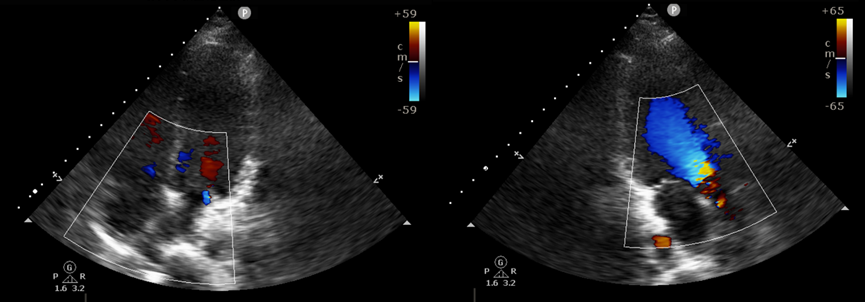

1120日,患者接受了体外循环辅助下房间隔缺损修补手术。在常规消毒铺巾、逐层打开进入心包后进行体外循环,停心后打开右心房,探查见最大缺损有3.5cm!在大缺损下另有三处小缺损,直径约0.5cm。马海涛主任仅用缝线操作,针走龙蛇,行云流水般的关闭了缺损,尽显精湛技术,并在关闭心脏后成功复跳。术后,在我院麻醉手术科、重症医学科、胸心大血管外科等科室的通力合作下,病人生命体征逐渐平稳,转入普通病房开始康复治疗,复查床边心超亦未见残余分流,患者现已顺利出院。